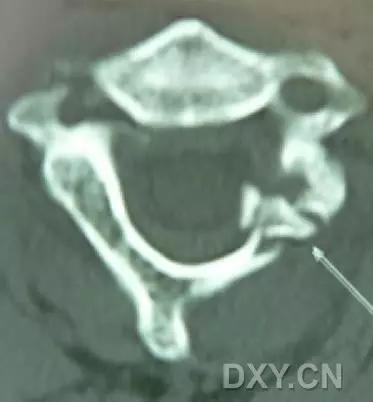

3. Chance 骨折

胸腰段椎体的分离性骨折,伴随脊髓、神经根、椎体的水平方向的崩裂骨折。又称座带骨折(seatbelt fracture)。

由 Chance 于 1948 年首先描述此骨折,故文献又常称 Chance 骨折,为一种屈曲拉伸骨折。典型的损伤机制为汽车座带束于患者腰腹部,当高速行驶的汽车突然减速或撞车时,座带支点以上的躯干屈曲,前冲力还同时产生一个向前拉伸的力量。将椎体由后方向前撕裂,骨折线横过椎体、椎弓根和椎板,椎体后部的韧带完全撕裂。有时前纵韧带亦可撕裂,常合并有神经系统的症状。

(来源:Radiopaedia)